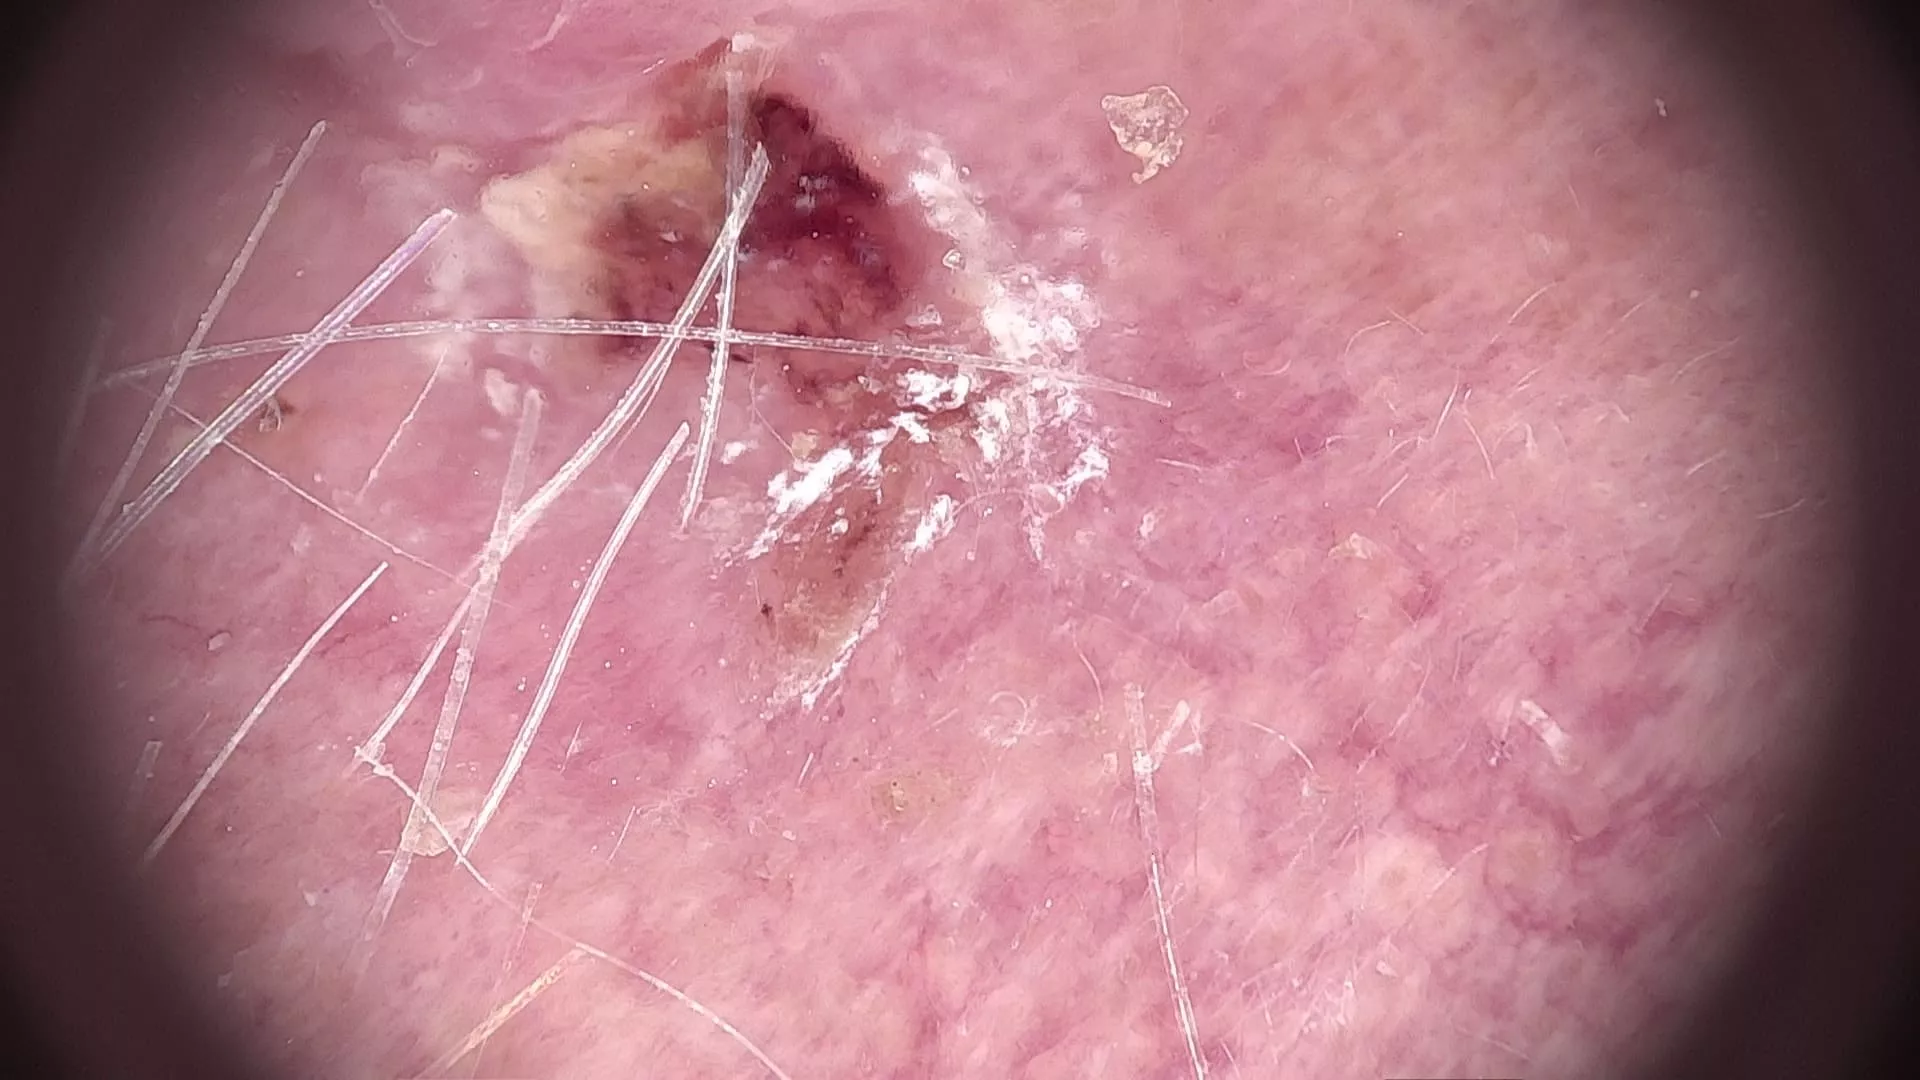

Beim Ganzkörperhautcheck in der mySkin Klinik ist dieses Melanom am Arm aufgefallen. Erst im Videodermatoskop sieht man die offensichtlichen Unregelmäßigkeiten.

Hier sieht man ein Melanom im Videodermatoskop. Die Ränder sind ungleichmäßig, die Begrenzung fransig, die Läsion ist mehrfarbig, ist im größten Durchmesse größer als 5mm.